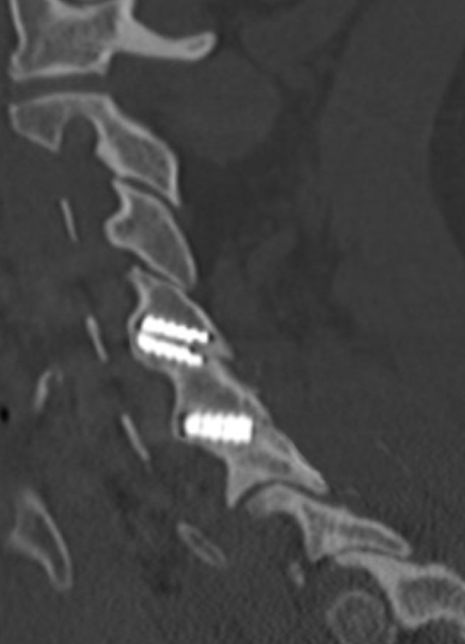

Sagittal CT image showing left anterior/posterior bone bridging.

Sagittal CT image showing anterior bone bridging.